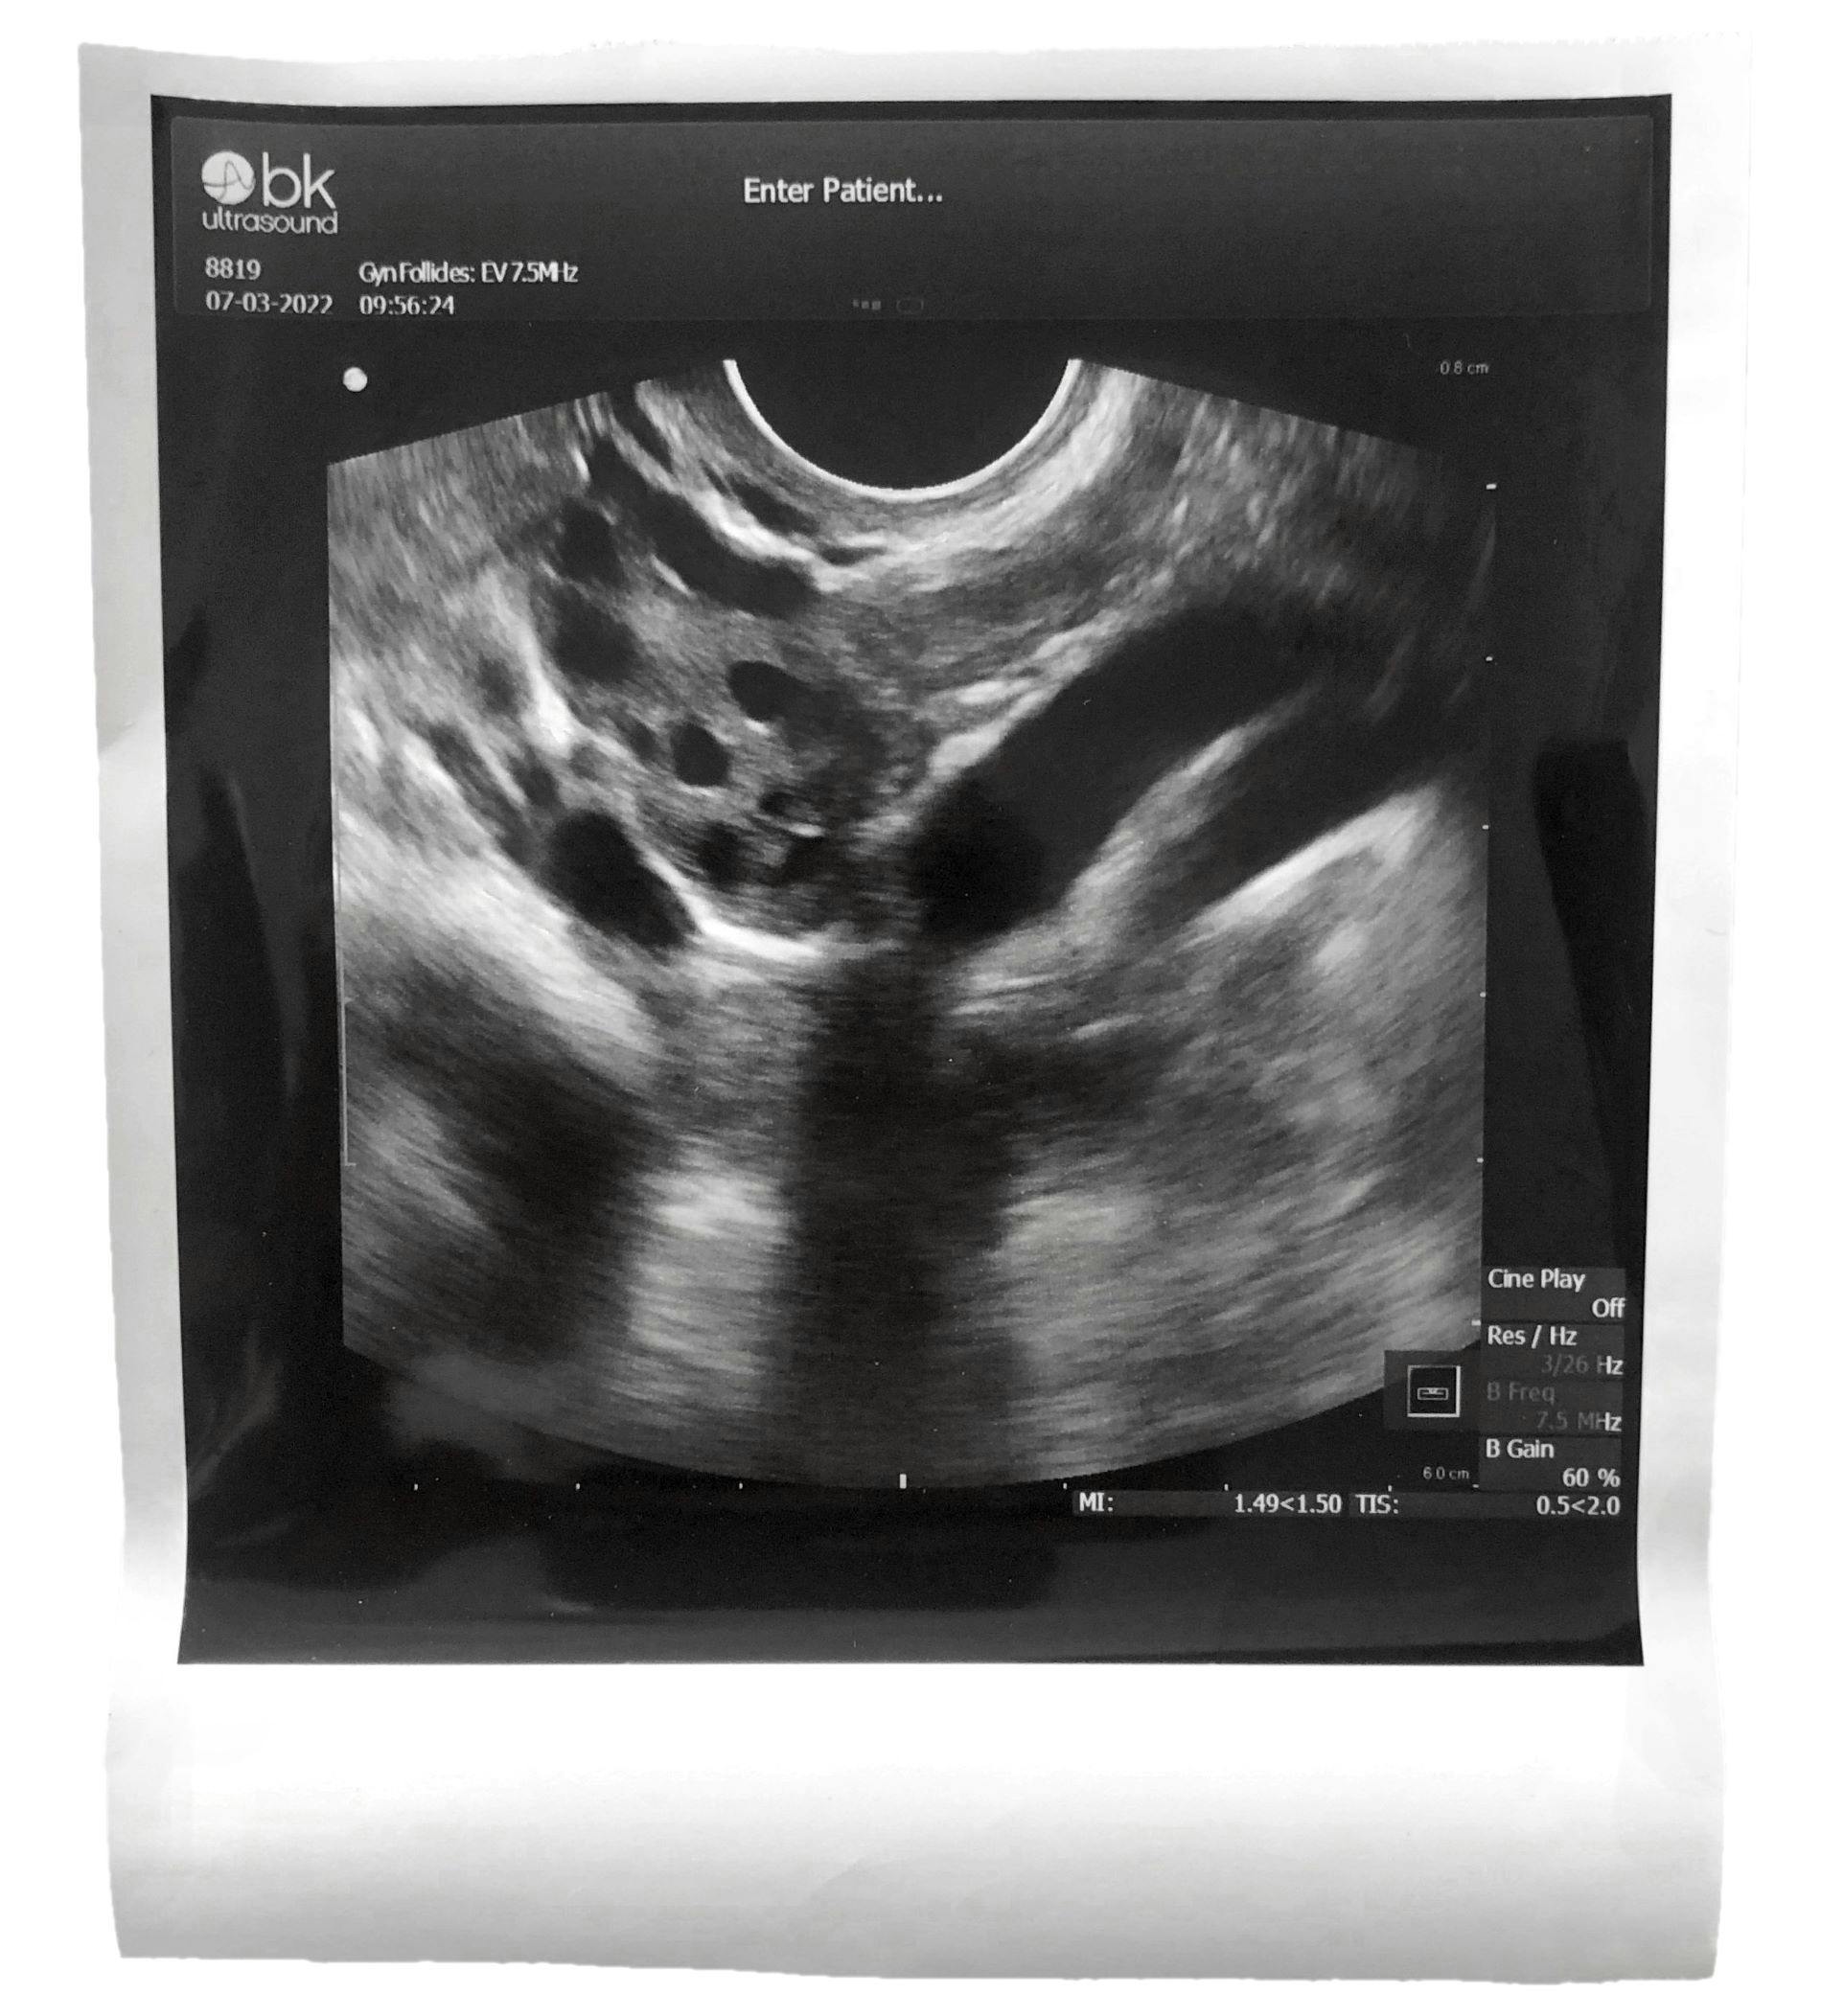

Jeg drejer hovedet for at se på en skærm, hvor noget, der ligner en graviditetsscanning, dukker op. Her er bare ikke noget foster, men mine æggestokke.

Først den venstre: Små sorte prikker afbryder det uklare hvide væv, og hun siger, at jeg har masser af æg, mens hun tæller dem: et, to, tre, fire, fem. Hun siger, jeg i hvert fald har 20-30 æg, at det er mange, og det samme gælder den højre æggestok.

Jeg spørger, om jeg må få et foto af det. Hun spørger lidt undrende hvorfor, og jeg svarer, at jeg bare synes, det er fascinerende.

Det er jo heller ikke løgn, det gør jeg, men jeg har mest af alt brug for et konkret bevis på noget for mig meget abstrakt: At der inden i mig svømmer nogle æg rundt, som betyder, at jeg i princippet kunne blive et barns mor.